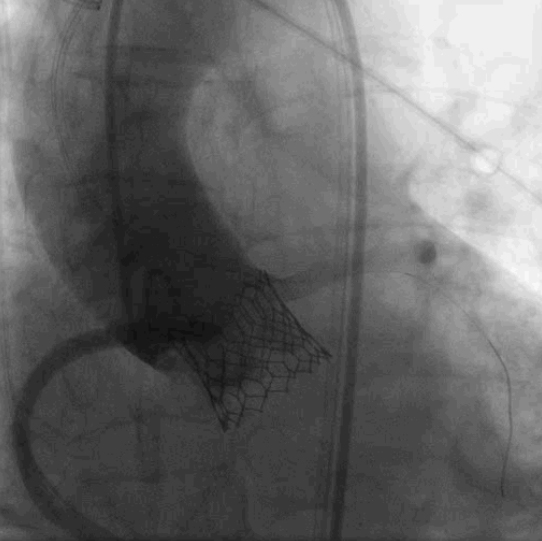

术中,患者突发室颤和血压下降,最凶险的情况还是发生了---冠状动脉阻塞!晋军教授及其团队果断决策、沉着应对,千钧一发之际为患者紧急开通血管,最终顺利将瓣膜精准释放到预期位置,手术圆满成功。

▲瓣膜定位造影